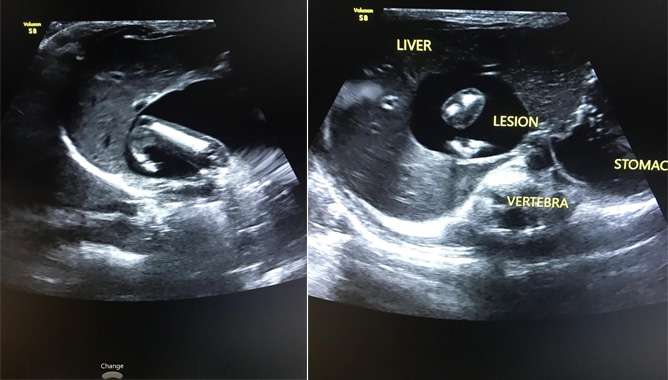

വയറിന് ഒരു തടിപ്പുണ്ട് എന്ന് മാത്രമാണ് പറഞ്ഞത്. ഉടന് തന്നെ സ്കാനിങ് ചെയ്തുനോക്കി. ആ ഘട്ടത്തില് ലിവറിനും കിഡ്നിക്കും ഇടയില് ഒരു ഫ്ളൂയിഡ് കണക്ഷനും കൈയും തലയും കാലും ഏതെന്ന് മനസിലാവാത്ത മറ്റൊരു അവയവും കണ്ടു. അപ്പോള് തന്നെ അതിന്റെ ത്രിഡി സ്കാനിങ് ചെയ്തു. അതിന്റെ ഇമേജുകളെല്ലാം പരിശോധിച്ചപ്പോഴാണ് ഇത് ഫീറ്റസ് ഇന് ഫീറ്റു എന്ന എക്സ്ട്രീമിലി റെയര് കണ്ടീഷനാണെന്ന് മനസിലാകുന്നത്. അങ്ങനെ ആ റിപ്പോര്ട്ടുമായി അവര് കോഴിക്കോട് മെഡിക്കല് കോളേജില് എത്തുകയായിരുന്നു.

കേരളത്തില് ആദ്യമായി ഇത്തരമൊരു രോഗാവസ്ഥ ഡയഗ്നോസ് ചെയ്യുന്നത് ഡോ. ഹരിയാണ്. ഫീറ്റസ് ഇന് ഫീറ്റുവിന്റെ ത്രിഡി ഇമേജുകളൊന്നും ഇതുവരെ ആര്ക്കും ലഭ്യമായിരുന്നില്ല.